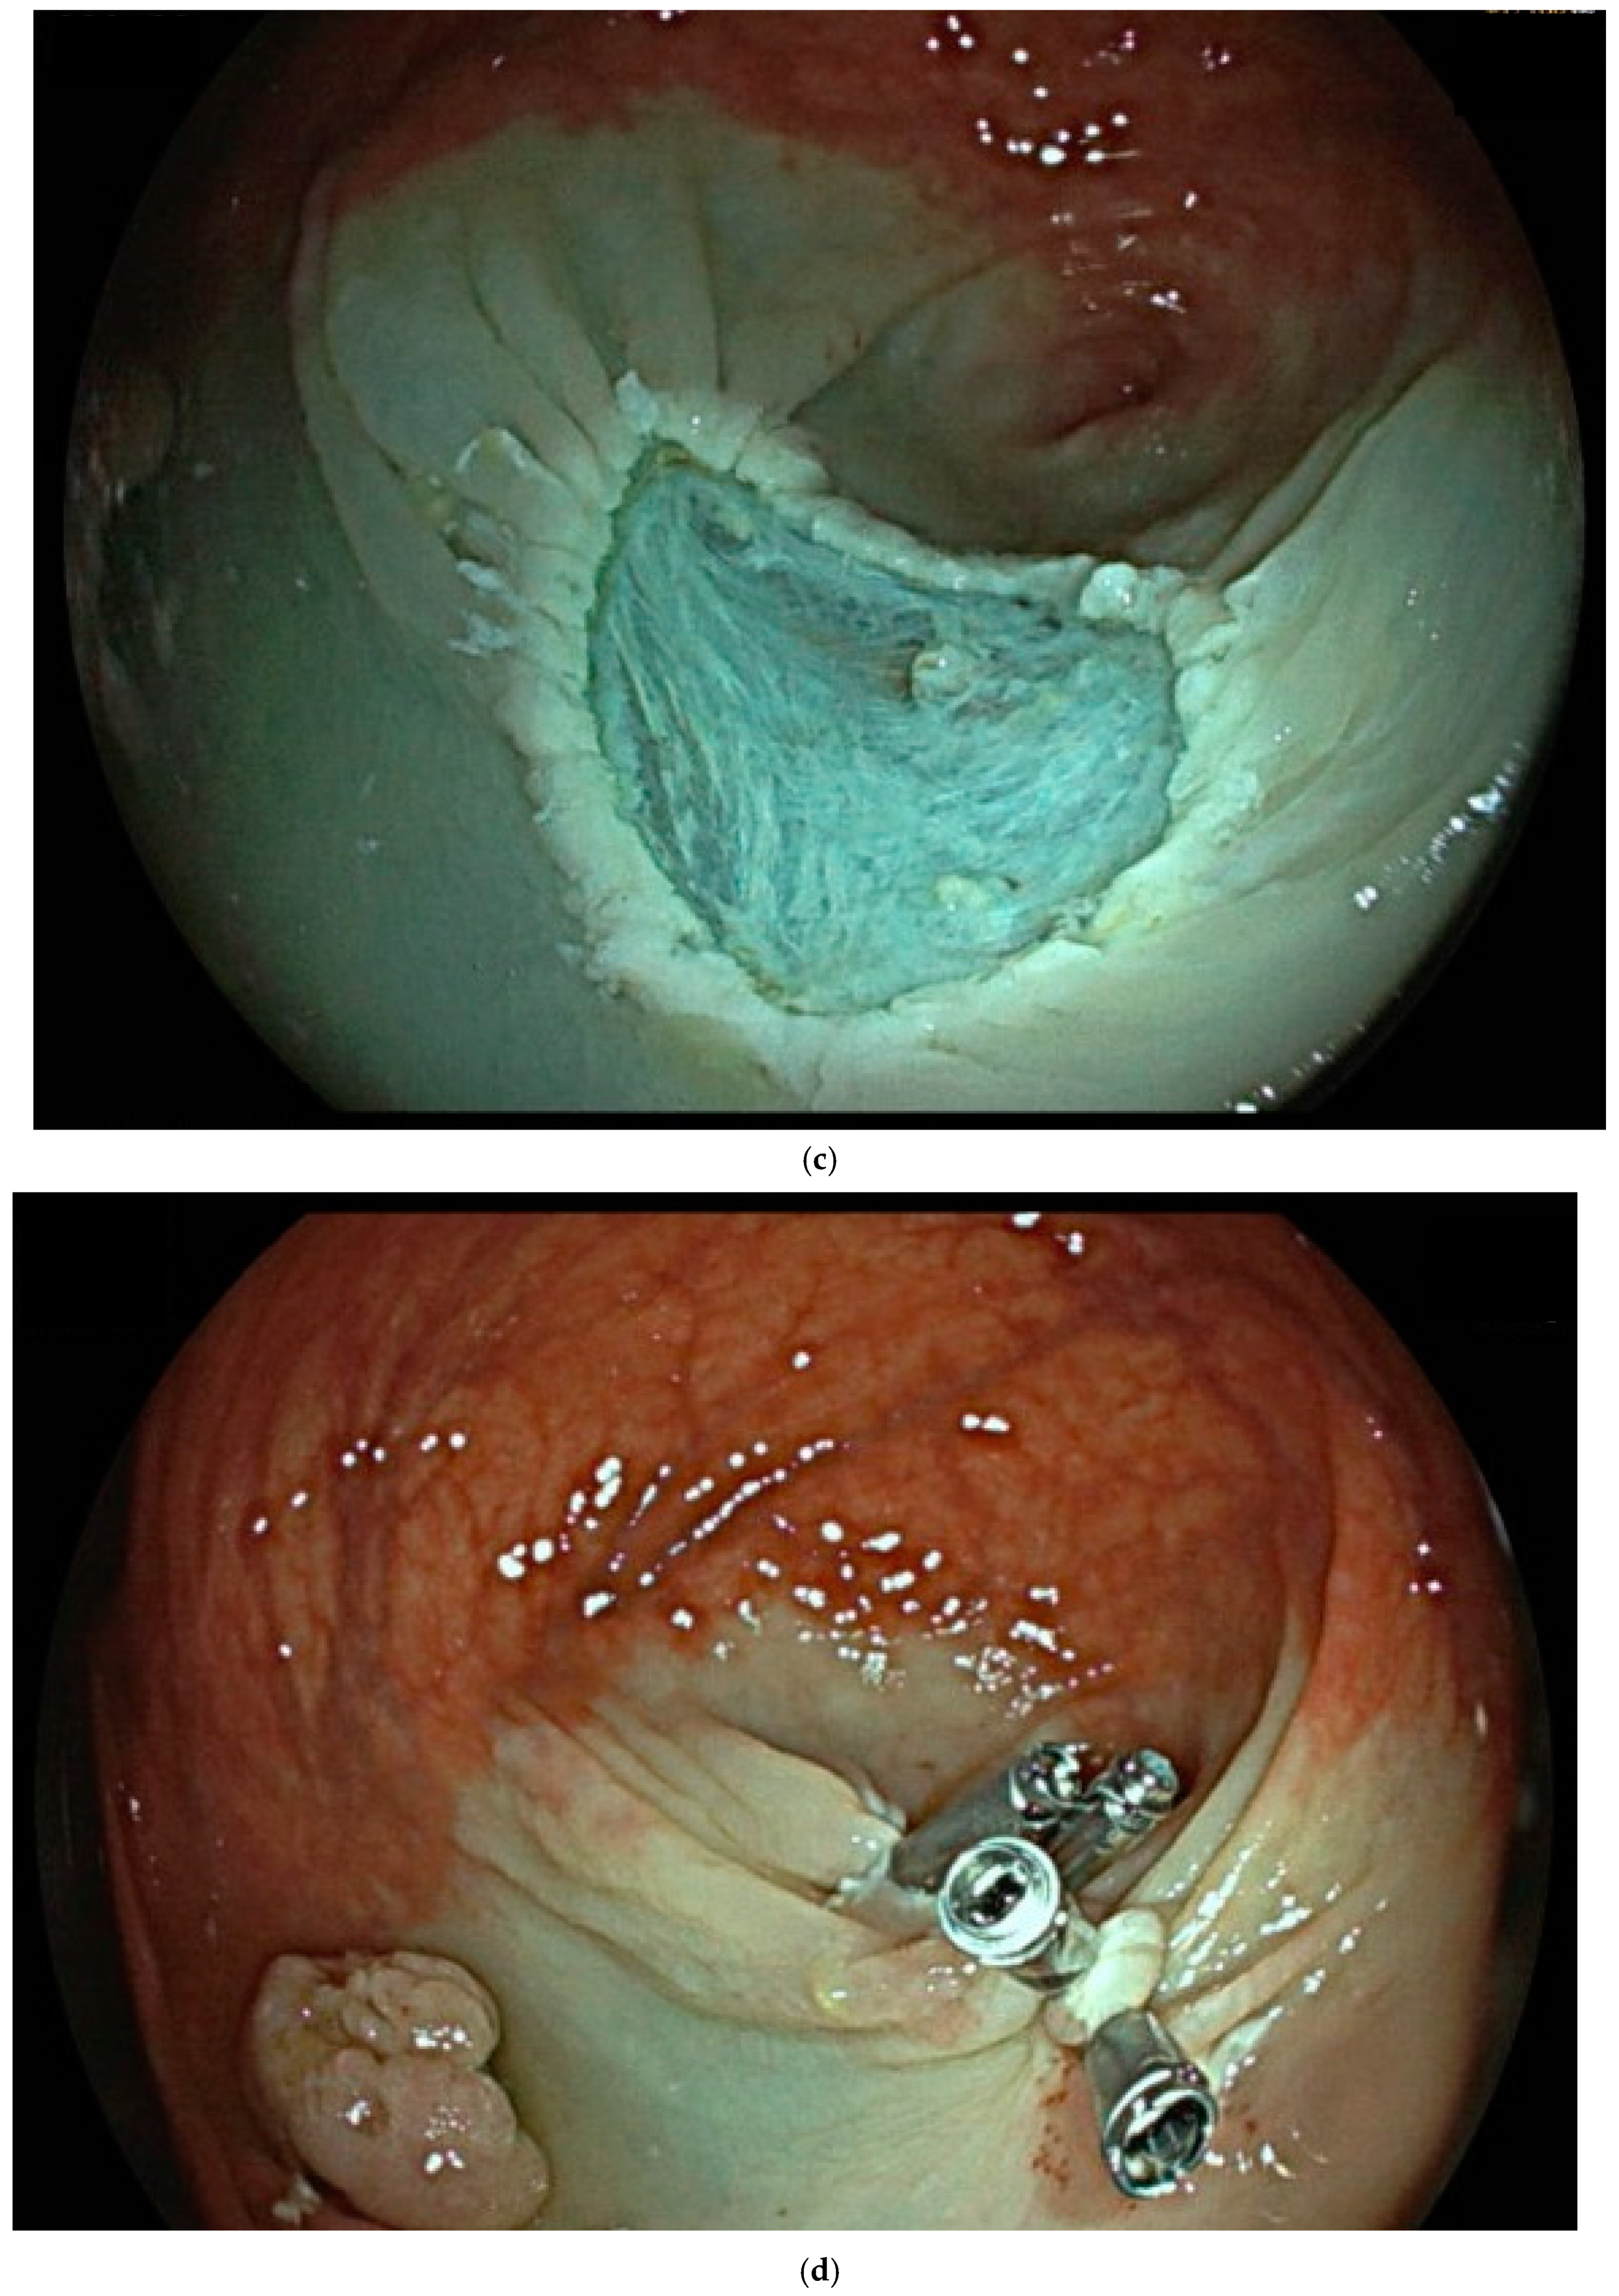

| Endoscopic mucosal resection (EMR) involves injection of a solution into the submucosal space in order to separate the mucosal lesion from the underlying muscularis propria. The lesion can then be resected by snare electrosurgery. The submucosal cushion theoretically reduces the risk of thermal or mechanical injury of the underlying muscularis propria [81]. | ![]() |

| Endoscopic submucosal dissection (ESD) is characterized by three steps: fluid injection into the submucosa in order to swell the lesion from the muscle layer and circumferential cutting of the mucosa surrounding the lesion, followed by dissection of the submucosal connective tissue beneath the lesion (standard technique). The major advantages of this technique in comparison with polypectomy or EMR include control of the resected size and shape, possible en bloc resection even in a large lesion and also resectability of the lesions in case of submucosal fibrosis. Disadvantages include the time-consuming procedure associated with a higher risk of complications (mainly bleeding and perforation) when compared with EMR [83]. | ![]() |